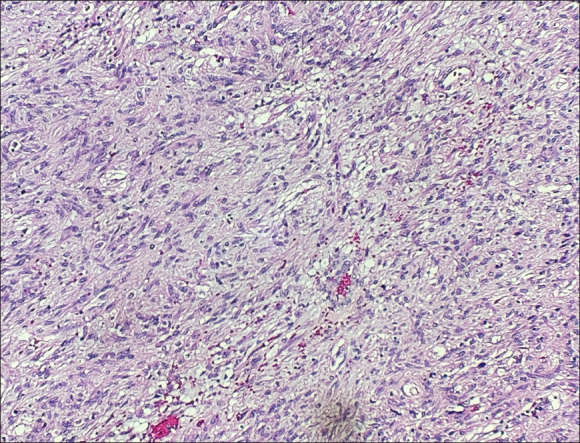

Abstract Image